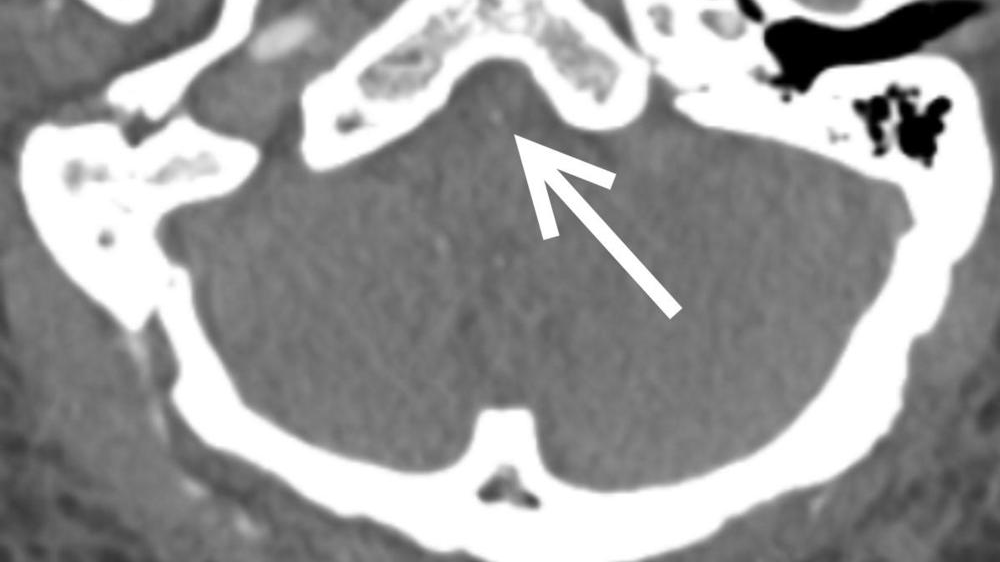

To learn more about the phenomenon, Dr. Freeman and colleagues in the Perelman School of Medicine at the University of Pennsylvania looked at COVID-19 patients who underwent head CT and/or MRI in their health system from January to April 2020. Of the 1,357 patients with COVID-19 admitted to the system in those four months, 81 had a brain scan performed. The most common reasons for the brain scans were altered mental state and focal neurologic deficits such as speech and vision problems.

Out of 81 patients with brain scans, 18, or just over one in five, had findings that were considered emergency or critical, including strokes, brain bleeds and blocked blood vessels. At least half the patients had pre-existing histories of high blood pressure and/or type 2 diabetes. Three patients with emergent/critical findings died while admitted.